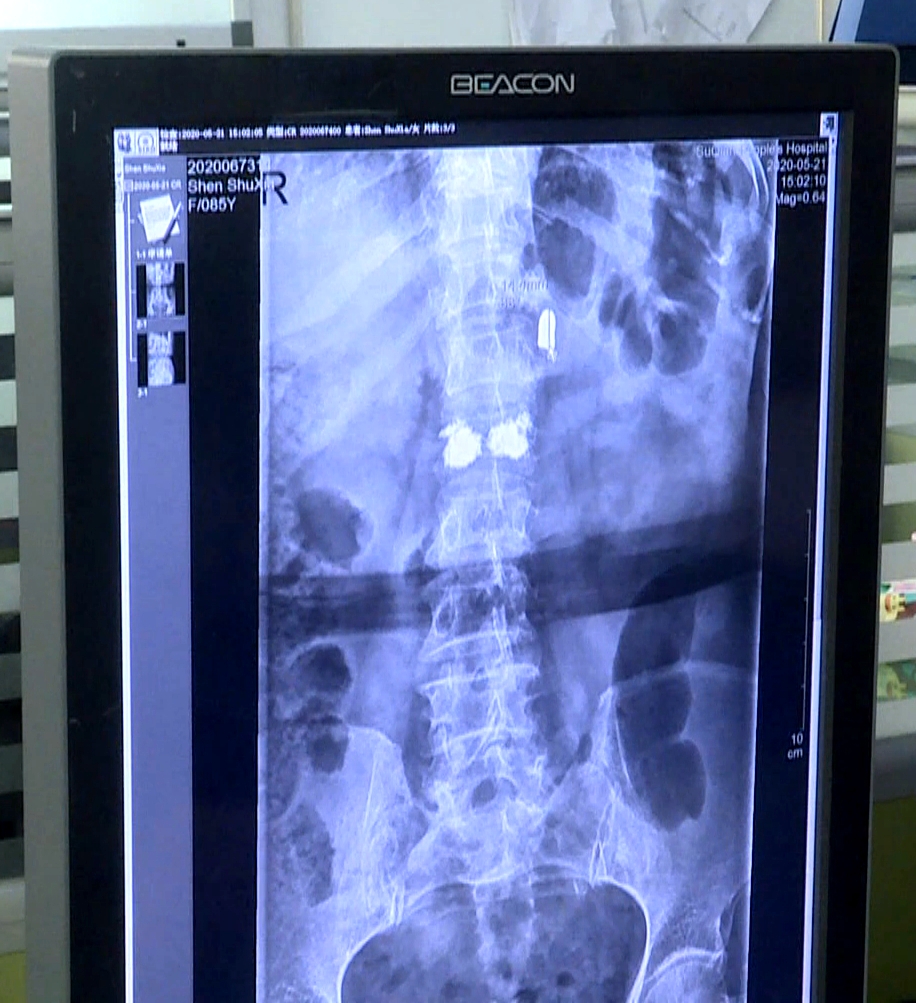

江苏省宿迁市的85岁老人沈书侠近日遭遇车祸,腰椎骨折。医生手术透视过程中,在老人背部发现了一枚子弹,直径8毫米左右,长度15毫米左右,像是手枪的子弹。老人这才回想起日本侵略者进村扫荡时,自己后背受伤侥幸存活,没想到子弹在体内留存了80年。

沈书侠昏迷中侥幸存活,事后被亲戚收养,抚育成人。八十年来,失去家人的伤痛和童年的阴影一直伴随着沈书侠老人,但她从没想到自己体内还有一颗子弹。尽管偶尔会感觉到腰部隐隐作痛,但总认为是自己腰不好。由于子弹头潜藏较深,距离老人的腰椎和其他器官较近,加上老人年事已高,手术具有一定风险性,医生不建议将子弹头取出。